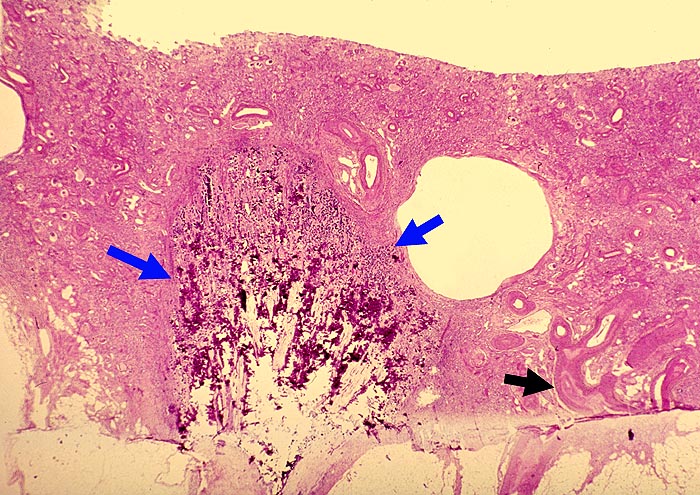

Analgetikanephropathie

Niere, Harnwege

Niere

Pathologischer Befund